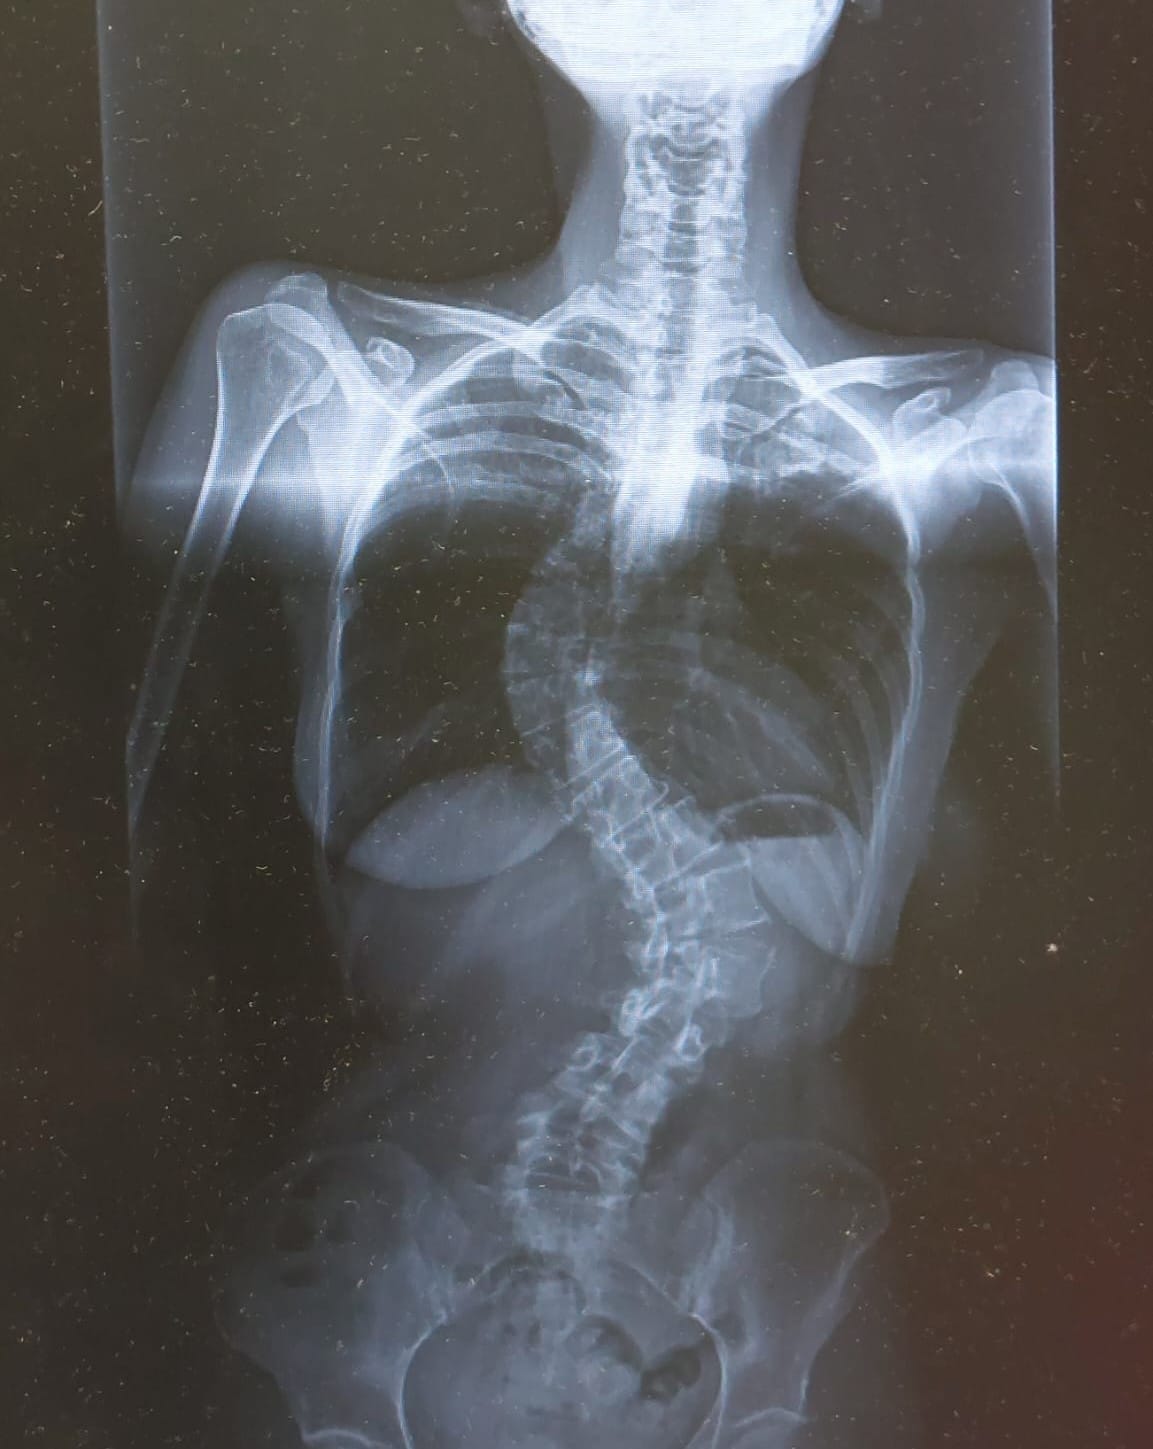

Severe scoliosis x-ray

Source: Susanne van de Munt

Spine deformity doesn't wait in quietness. Spine deformity challenges your body and your mental strengths among other daily inconveniences in a hard way.